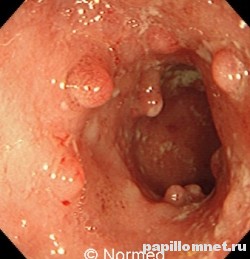

Фото полипов в прямой кишке, которые необходимо удалить

Первая бессимптомная стадия болезни может протекать в течение нескольких лет. Быстрота увеличения новообразования в размерах и присоединение других множественных образований зависят от состояния слизистой. Симптом, по которому можно заподозрить наличие опухоли прямой кишки,- это выделение слизи при опорожнении кишечника. Большой по размеру полип может частично или полностью закрыть просвет в органе, в этом случае регистрируются такие симптомы, как запор, примесь крови в кале. Из нижних отделов кишки при нарушении целостности новообразования или при его изъязвлении выделяется кровь алого цвета.

- Ворсинчатый тип полипа характеризуется наличием мелких ворсинок на поверхности, имеет ярко–розовую окраску, форма круглая или вытянутая. Ворсинчатый полип склонен к малигнизации.